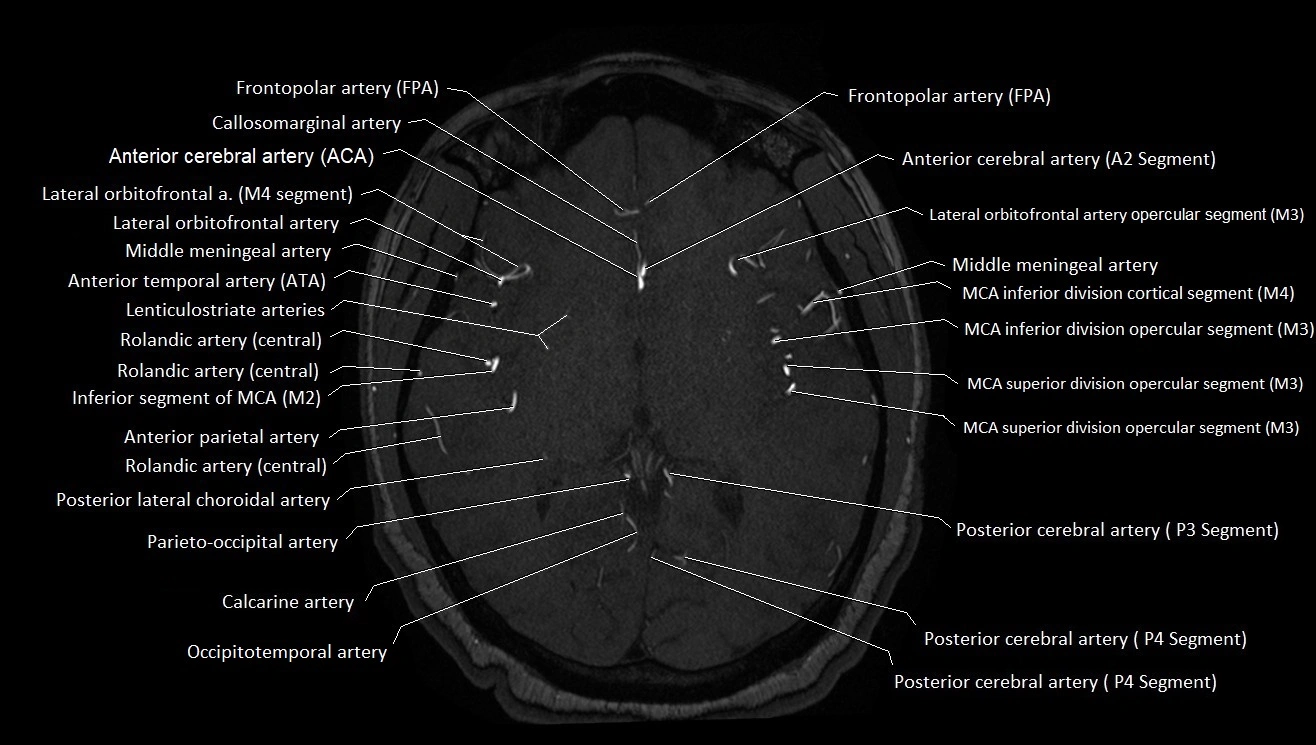

MRI images

image